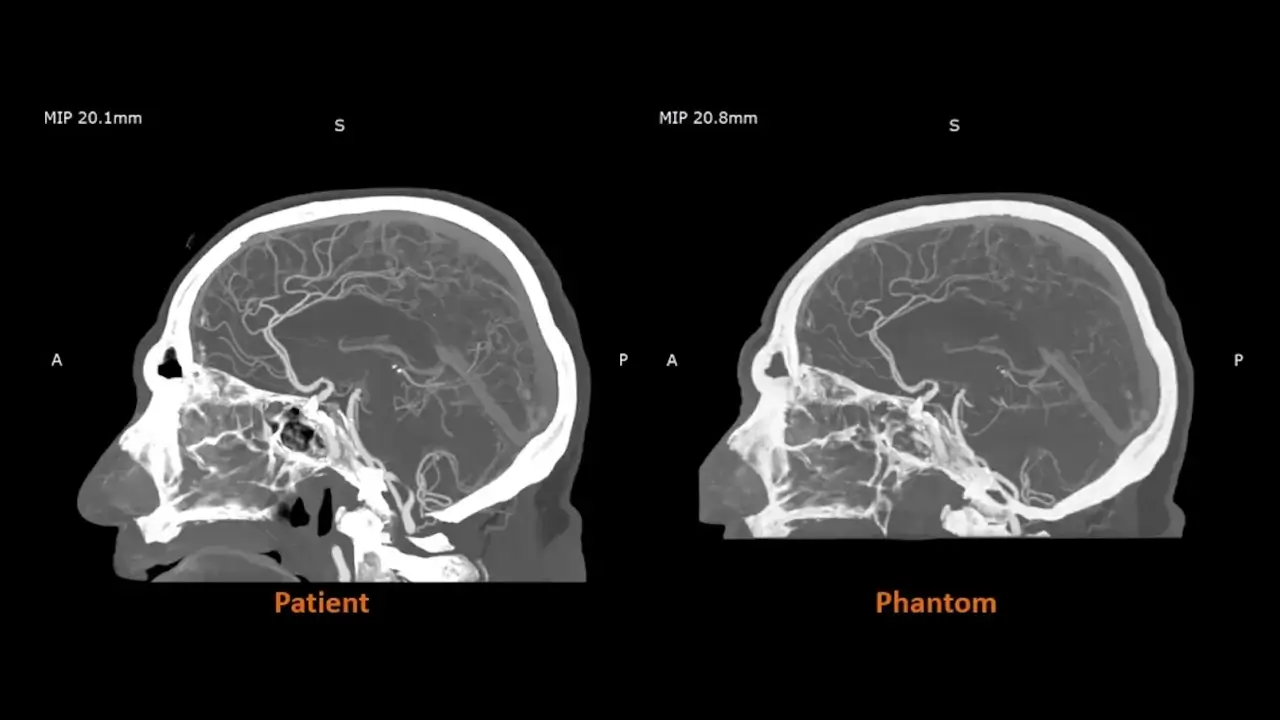

Un trabajo en el Reino Unido con socios como CPI y el Hospital Beaumont ha demostrado el impacto de los modelos radiopacos impresos en 3D en la práctica. Se utilizan fanálogos de angiografía cerebral radiorrealistas para mejorar la fidelidad del entrenamiento basado en imágenes y crear entornos de investigación más controlados y repetibles.

Las primeras investigaciones de la colaboración Stratasys–Siemens Healthineers muestran que los fanálogos RadioMatrix impresos en 3D pueden replicar fielmente el tejido humano real en imágenes de TC, con desviaciones reportadas de tan solo una unidad Hounsfield (UH) en áreas críticas, como la materia gris y las venas.

Al combinar la tecnología de impresión 3D de Anatomía Digital de Stratasys y materiales radiopacos con algoritmos avanzados de imagen, los socios han desarrollado fanálogos anatómicamente realistas y radioprecisos que conservan detalles anatómicos precisos y variaciones patológicas, a la vez que ofrecen una alternativa más consistente y ética a los cadáveres.